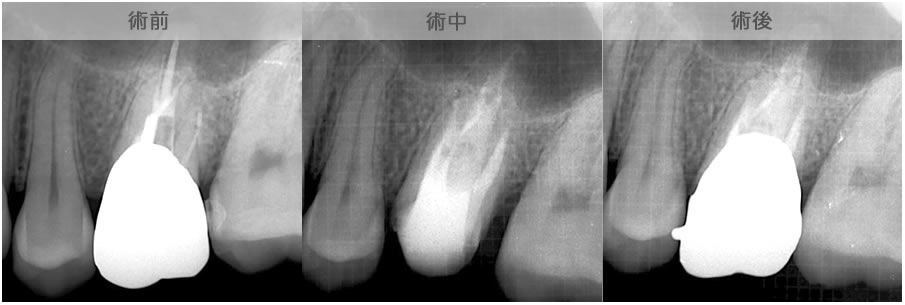

| 1.丸の中の黒く写っているところが 感染している状態です。 |

2.矢印が指しているのが根管です。 そこへお薬を詰めます。 |

3.黒い影が消え、白くなりました。 これで感染源もなくなりました。 |

| 治療説明 | 上顎前歯部の根尖部からの排膿があります。歯冠補綴物とメタルコアを除去し、根管治療を行いました。根尖部から根充剤が漏れてはみ出していましたが、X線透過像は消失しました。 |

|---|---|

| 治療場所 | 上顎前歯部 |

| 原因 | 根尖病巣 |

| 治療期間 | 6〜24ヶ月 |

| 治療費用 | 150,000〜300,000円 |

| 治療に伴うリスク | 根管内からの治療で根尖病巣が治らない場合は、外科的に根尖病巣を除去する必要があります。 再根管治療を繰り返す場合、歯根の厚みが薄くなり、歯根破折のリスクが高まります。 |